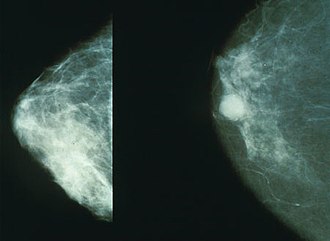

Mamografija je točna i sigurna rendgenološka pretraga (danas se koristi samo pedeseti dio doze zračenja potrebne u početku) kojom se otkrivaju tumori i druge promjene, premalene da bi se mogle napipati. Mamografski pregled u većini slučajeva nije bolan. U mladih žena žljezdano tkivo zauzima gotovo cijelu dojku i mamografska slika je prilično nejasna, stoga je uobičajeno da nema razloga (osim iznimno) snimati dojke žena mlađih od 35 godina. Prvu mamografiju tzv. bazični (inicijalni) mamogram savjetuje se napraviti ženama između 38. i 40. godine, a zatim ženama starijim od 40 godina jednom godišnje. U žena u dobi od 50-69 godina preporuka je mamografiju napraviti minimalno jednom u dvije godine. Mamografija obuhvaća dvije snimke dojke uz maksimalno stlačivanje dojki (pritiskom na dojku kompresijskom pločom), snimku dojke sprijeda te s njezine bočne strane, koje prikazuju njezinu građu i sumnjiva mjesta. Unatoč nezamjenjivosti mamografije u ranom otkrivanju i najmanjih karcinoma, važno je naglasiti da se mamografijom ne može prikazati 15-20 % karcinoma dojki, osobito kad se radi o dojkama s gustom žljezdanom strukturom. U Hrvatskoj se radi dogovora za mamografiju treba javiti svom izabranom liječniku obiteljske medicine ili ginekologu.